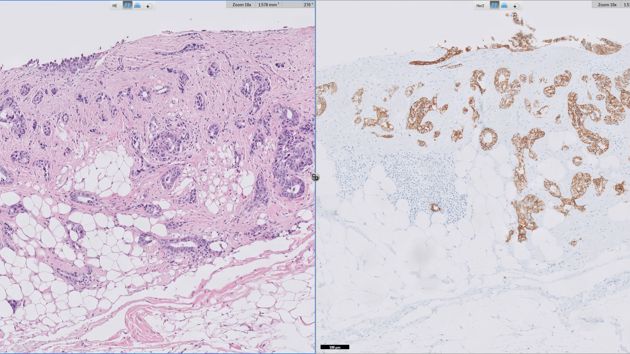

IHC-dag over Farmacomarkers

Enthousiaste sprekers geven op deze dag uitleg over immuun kleuringen in de diagnostiek in combinatie met therapie en behandelplan.